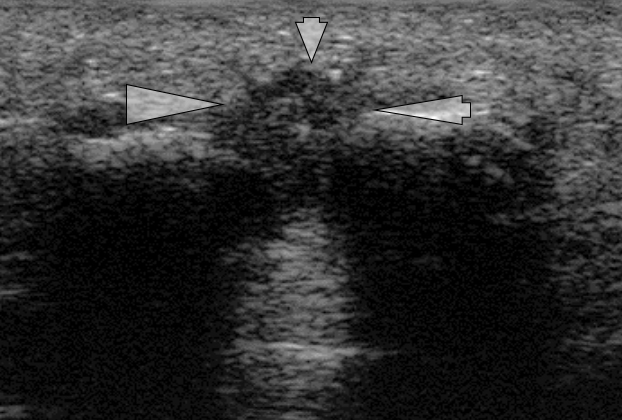

L’indagine ecografica, con precise specifiche tecniche nei dettagli esecutivi, si è dimostrata nel corso degli anni la metodica più affidabile per la diagnosi di neuroma di Morton.

Tecnicamente parlando si richiede ecografia dinamica avampiedi secondo Shapiro, Perini e Torriani con manovra ecografica di Mulder, dal nome degli autori che hanno via via messo a punto una diagnostica ecografica affidabile per questa patologia.

All’esame, che va condotto con scansioni ecotomografiche plantari e dorsali con sonda ad alta frequenza da 7.5 MHz, la masserella appare omogeneamente ipo-ecogenica, ben riconoscibile dal grasso iperecogenico adiacente e l’ombra delle corticali metatarsali.

Nella manovra ecografica di Mulder si lussa manualmente dal lato plantare la masserella neuromatosa, che poi scatta di nuovo verso la pianta del piede nella manovra di avvicinamento delle dita.

Secondo Perini, con questa tecnica è più facile identificare la masserella, che si riconosce più agevolmente nel suo spostamento e si può più facilmente misurare nelle sue dimensioni; l’esame diventa così significativo per masserelle dai 3,8 mm in su.

Secondo Shapiro e poi Quinn, ci si può attendere un’affidabilità diagnostica intorno al 95% per masserelle superiori ai 5 mm, essendo di 2 mm il limite massimo del nervo normale

Riteniamo dunque di 3,8 mm il valore di cut off per diagnosi certa di neuroma di Morton.